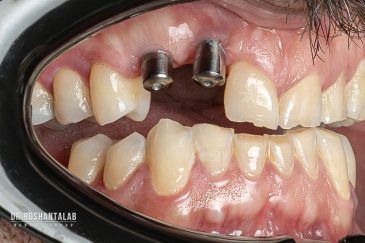

کلینیک تخصصی دکتر حسن روشن طلب با همکاری جمعی از متخصص ایمپلنت دندان و جراح فک و صورت بنام در حال فعالیت می باشد. این مجموعه مأموریت خود را ارائه خدمات تکمیلی دندانپزشکی در زمینه درمان های تخصصی و عمومی به شرح ذیل انجام می شود.

🔸 کاشت ایمپلنت دندان بدون درد

🔸کاشت ایمپلنت فلپ لس یا بدون جراحی و بدون بخیه زیر سه دقیقه

🔸 کاشت دندان یک روزه ( کشیدن و کاشت همزمان )

🔸 ایمپلنت دیجیتال و ساخت روکش دیجیتال